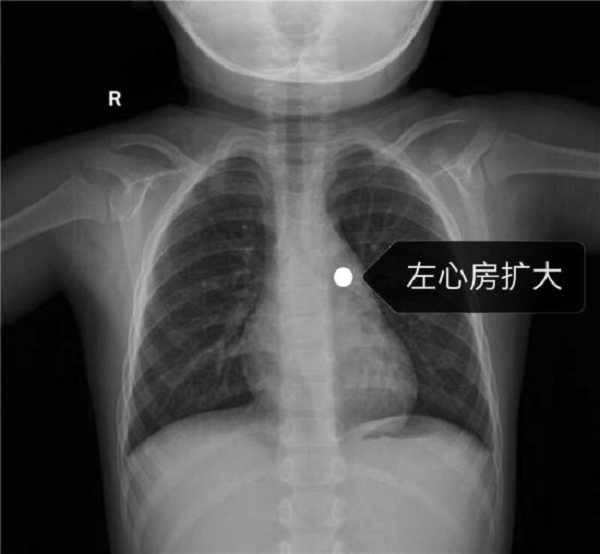

患者为4岁男性患儿,体检发现先天性心脏病:动脉导管未闭,分流4.3mm,且左心房已经扩大,来我院就医希望能得到进一步及时诊治。